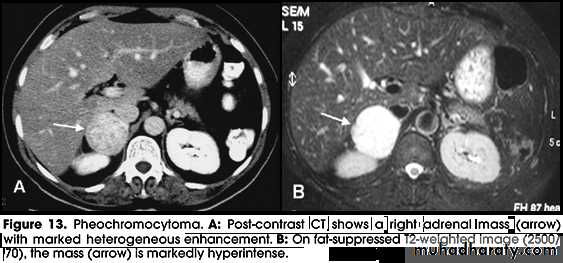

• Phaeochromocytoma is a tumour arising from chromaffin cells of the adrenal medulla.

• Ninety per cent occur in the adrenal gland and 10 per cent in ectopic extra-adrenal locations.

• Phaeochromocytomas are usually large tumors, measuring up to 12 cm with an average around 5 cm.

• Imaging of Phaeochromocytomas includes:

• CT of the abdomen, with particular attention to the adrenal glands is the initial imaging investigation of choice in the diagnosis of phaeochromocytoma.

• MRI of the abdomen may be used where MIBG is not available.